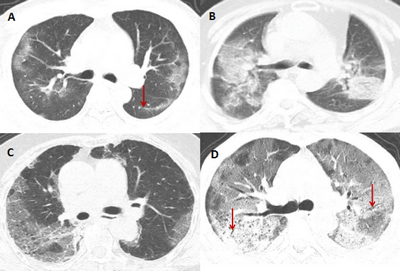

Хронічні обструктивні захворювання легень (ХОЗЛ)

КТ може виявити емфізему та хронічний бронхіт, які є поширеними типами ХОЗЛ. Ці дослідження також можуть допомогти визначити тяжкість захворювання та найкращий курс лікування.

Пневмонія

КТ може виявити ділянки запалення в легенях, які є ознаками пневмонії. Ці сканування також можуть допомогти визначити ступінь тяжкості інфекції та найкращий курс лікування.